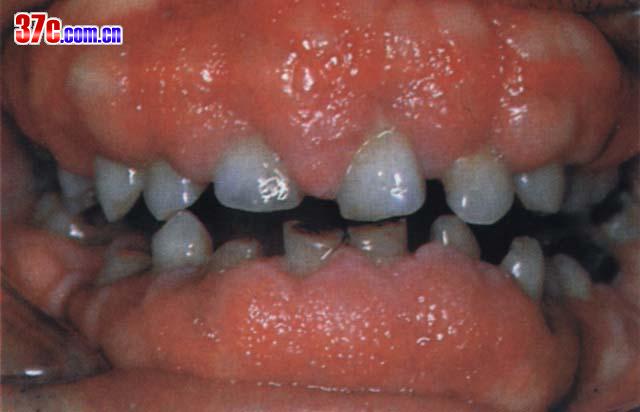

口腔牙龈增生图片